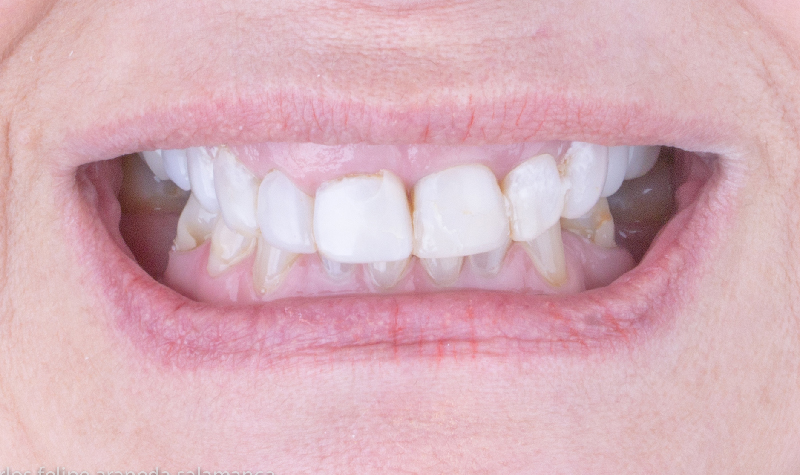

Diseño de Sonrisa Digital con carillas de cerámicas.

Cirugía de encia y Diseño de Sonrisa Digital con carillas de cerámicas.